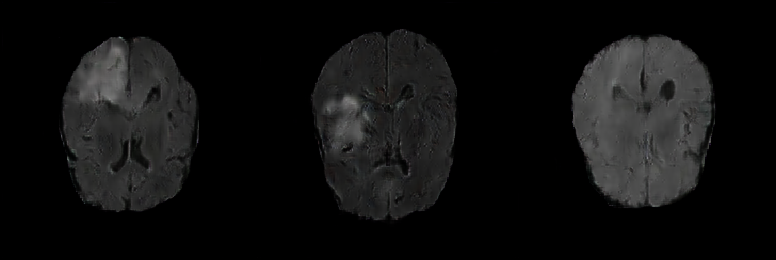

Generated Images Figure 5 shows the generated brain tumor FLAIR samples from -GAN-GP, PGGAN, and PGGAN-SSIM in AXI. The generated samples from all models look realistic and are close to the real images, where the white areas (Gliomas area) are concentrated and unified, indicating the training stability with gradient penalty. However, the samples from -GAN-GP are blurry, and the detailed brain features disappear since the loss of image information becomes serious when the image resolution increases in -GAN-GP. The generated samples from PGGAN and PGGAN-SSIM have clear and realistic brain features (FLAIR texture and tumor appearance) with diversity, which illustrates that PGGAN architecture is a well-suited model to generate brain MR images.

We also investigate MS-SSIM to evaluate the diversity of the generated distribution. The MS-SSIM score is obtained by calculating the average from 2000 sample pairs. The similarity between the generated samples by -GAN-GP is significant, suffering from mode collapse. The PGGAN and PGGAN-SSIM have similar MS-SSIM scores to real data, evenly PGGAN-SSIM outperforms the real data, which means that the generated samples have more diversity. Therefore, the structure of PGGAN can effectively avoid mode collapse, and the SSIM loss function can further improve the performance.

Ablation Study We also explore the effect of different input sizes and SSIM loss function. It can be seen from Table 1 that when the input size changes from 512 to 1024, the FID and MS-SSIM scores of all models become higher. The best results of this experiment are obtained by using a moderately sizeable latent vector size of 512. There is a trade-off balance between w/o SSIM loss function. When adding an SSIM loss function to the generator in PGGAN, the MS-SSIM scores are improved below the real data while the FID scores are a bit degraded. Since our objective is data augmentation that needs more samples different from real data, we suggest adding the SSIM loss function to improve the sample diversity.